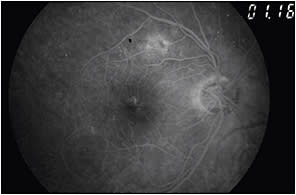

Perfusion status. The perfusion status of the macula and retinal periphery with ischemia (Figures 13 and 14) indicates a poor prognosis with no beneficial treatment. Such cases can present as a large foveal avascular zone (FAZ) or a FAZ with irregular borders.

Figure 13. Fundus photo of featureless retina with signs of macular ischemia. BCVA was counting figures.

Figure 14. Fundus FA of the patient in Figures 12 and 13 shows a large FAZ and capillary dropout.